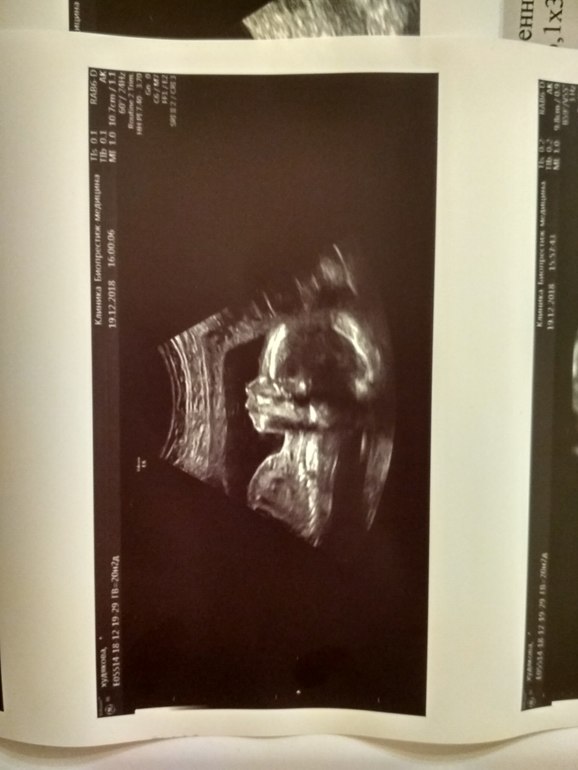

2 скрининг (20 и 4 дня)

Всё у него хорошо, вес 365гр, рост 23см, сердце 148 уд\м, нос 6,1

Вертелся крутился во все стороны, фоток вменяемых меньше, чем в первый раз, но лицо уже человеческое )))